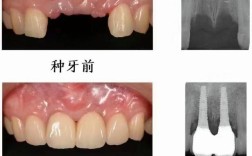

牙齿缺失后,若不及时修复,邻牙会向缺隙倾斜,对颌牙伸长,导致咬合紊乱、食物嵌塞、牙周病等问题,甚至影响面容和发音,种牙的核心优势在于其“独立性”——通过外科手术将纯钛种植体植入牙槽骨作为人工牙根,再在其上安装牙冠,无需磨损邻牙,且能刺激牙槽骨避免萎缩,恢复接近天然牙的咀嚼功能和美观度,以下情况通常建议优先考虑种牙:

- 单颗牙缺失:若不想磨切健康的邻牙(如固定桥修复需磨小邻牙),种牙是更保守的选择,能独立承担咀嚼力,不影响邻牙。